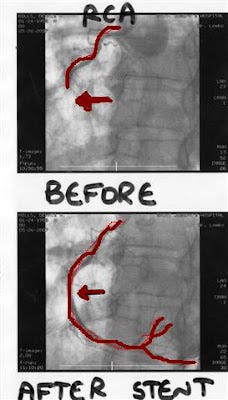

I can't feel anything, but the tubes are winding their way toward my heart. The doctors are conferring, and I get the feeling they are plumbing the clog with the 'snake" they have wormed its way into my hear. The one in charge stops for a moment to show me a photo- a black and white version of the one I have "doctored" at the top of this post. "This is your right coronary artery before we inserted the stent; and this is your right coronary artery after. You can see that the artery was 100% blocked. Now it is clear and open. We don't know now what the damage to your heart has occurred as a result of this myocardial infarction; we will keep you here for a few days, and you can see your doctors in Canada to take care of the other arteries with less than 100% blockages. "